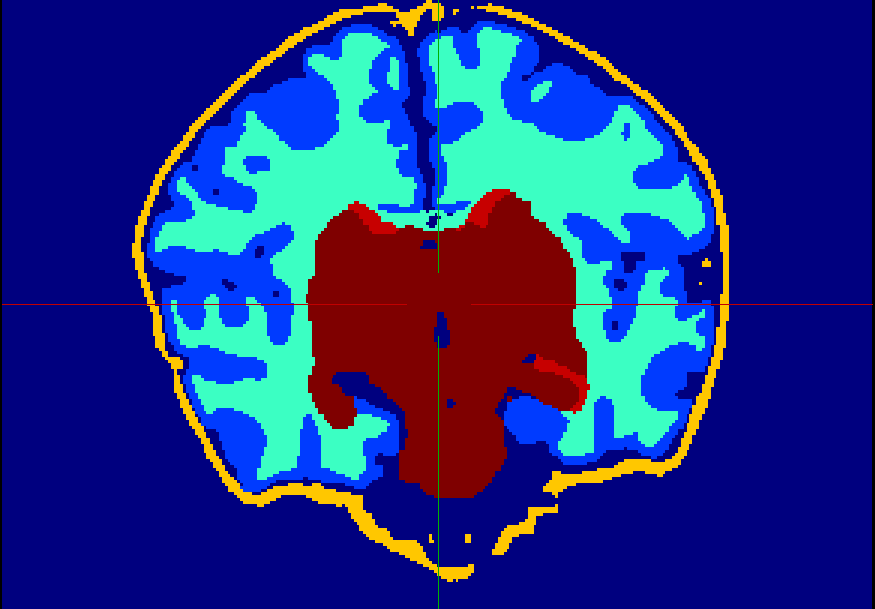

The dataset consisted of 70 3D T2-weighted brain MRI scans publicly available from the dHCP neonatal cohort. The segmentation maps had 10 classes, corresponding to: zero-pixel background, cerebrospinal fluid (CSF), cortical grey matter (cGM), white matter (WM), background bordering brain tissues, ventricles, cerebellum, deep grey matter (dGM), brainstem, and hippocampus. The scans covered an age range of 24.3-42.2 weeks. The data was available in NIfTI format; Figure 1 shows an example scan and corresponding tissue labels. We carried out a pre-processing step where each scan was independently normalised to zero-mean and unit-variance.